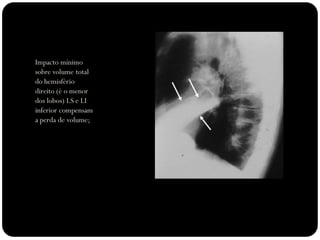

Impacto mínimo

sobre volume total

do hemisfério

direito (é o menor

dos lobos) LS e LI

inferior compensam

a perda de volume;